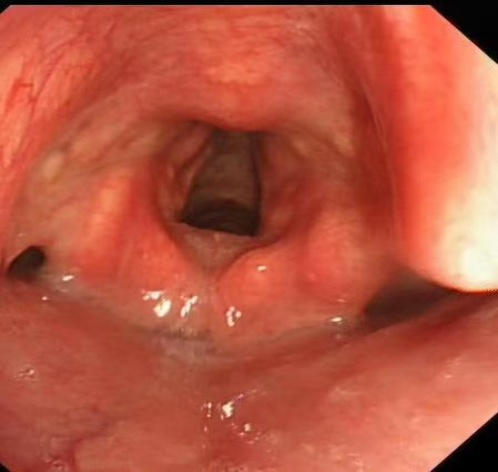

病例二:患者罗伟,男,37岁,矿业工人,因“胸闷、气短20天,加重伴右侧胸痛1天”入院。患者20天前出现活动后胸闷、气短,偶有咳嗽、咳痰,自行口服抗感染药物无效。入院后肺部CT显示双肺弥漫性斑片状磨玻璃密度增高影及网格影,双肺下叶微结节(部分钙化),考虑双肺间质性病变及PAP可能。支气管镜检见气管及支气管黏膜正常,右下叶外基底段亚支远端行支气管透壁活检。病理结果显示右肺下叶肺泡腔内粉染无定型物,PAS染色阳性,倾向PAP诊断。

入院评估与初步检查:① 入院后完善肺CT检查,结果显示双肺弥漫性斑片状磨玻璃密度增高影及网格影,双肺下叶微结节(部分钙化),考虑双肺间质性病变及PAP可能。② 行支气管镜检查:观察气管及支气管黏膜正常,管腔通畅。于右下叶外基底段亚支远端行支气管透壁活检,使用活检钳取肺组织4块,标本送检病理。③ 同时于右中叶外侧段行肺泡灌洗,使用生理盐水100 ml,回收60 ml灌洗液,留样送检。④ 病理诊断与特殊染色:肺组织病理检查显示右肺下叶肺泡腔内粉染无定型物。⑤ 特殊染色结果:PAS染色呈阳性,粘液卡红染色阴性,结合HE形态及临床表现,倾向诊断为PAP。